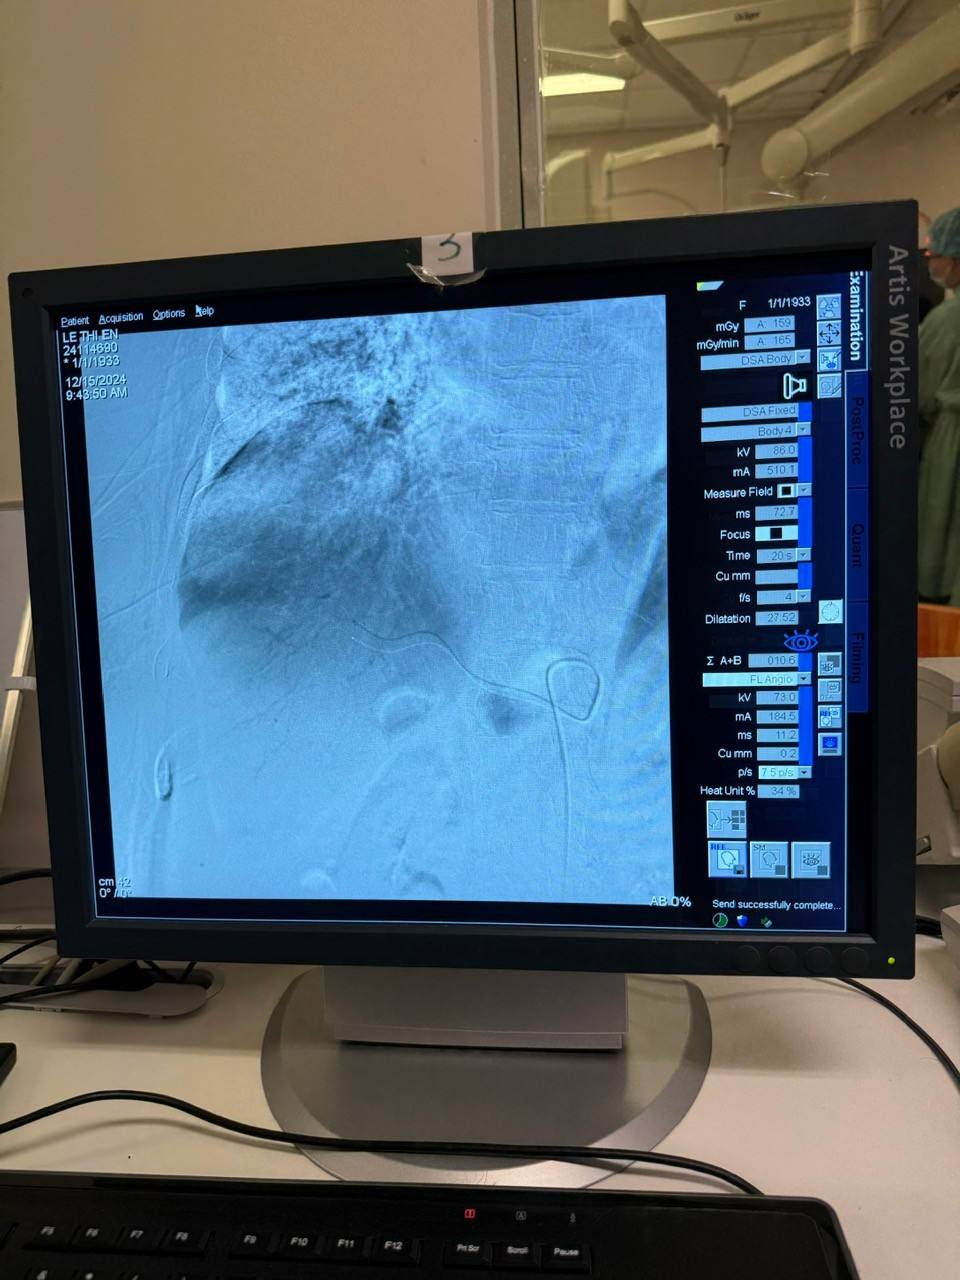

Hình 2: Cathete đang được dẫn vào vị trí khối Ung thư gan